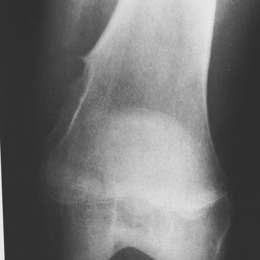

Radiographic imaging is used to help form a diagnosis. These include X-Ray, MRI, CT and Bone Scans

An example of a X-Ray is shown.